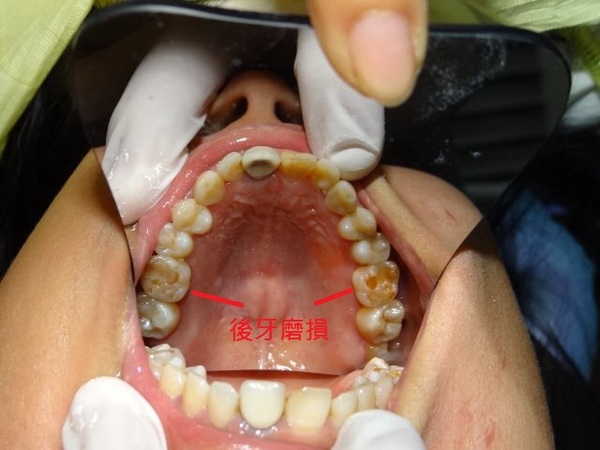

患者於就醫時表示:牙齒已做過幾次但都無法使用的很好,常常破裂,咀嚼不順,因此想獲得

改善,經醫師檢查後-發現患者有很大的咬合問題,除因缺牙造成的牙齒移位外,仍有智齒干

擾的多重因素,因此建議患者做全口整合性治療,並為患者設計療程。

治療前狀況..